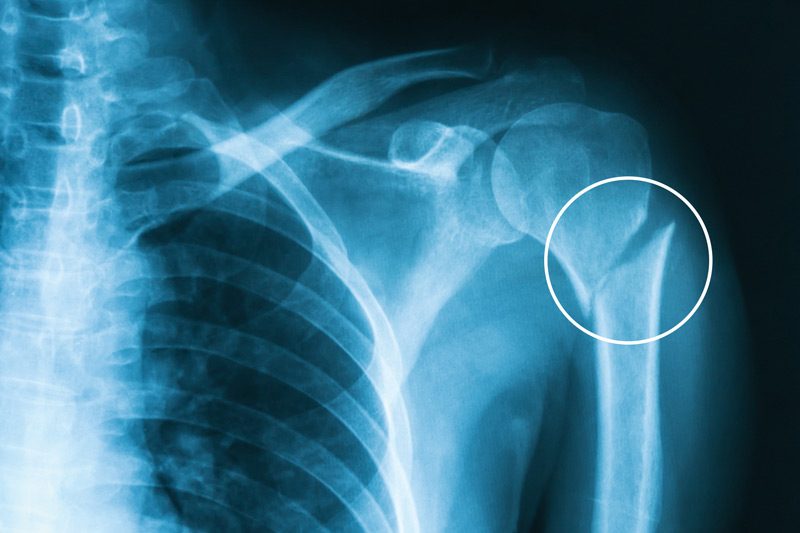

Humerus Fracture Types Symptoms Treatment

Let them decide what you need because that is exactly what they are there for. Do you have a digital X-ray walk-in clinic in Bradenton FL. An X-ray is a diagnostic imaging tool used to create pictures of the inside of the body.

X-rays for Broken Bones Injuries and More. Ad Get The Care You Need Today. X-rays are the most basic form of imaging tests which are diagnostic procedures used to view the bodys internal structures.